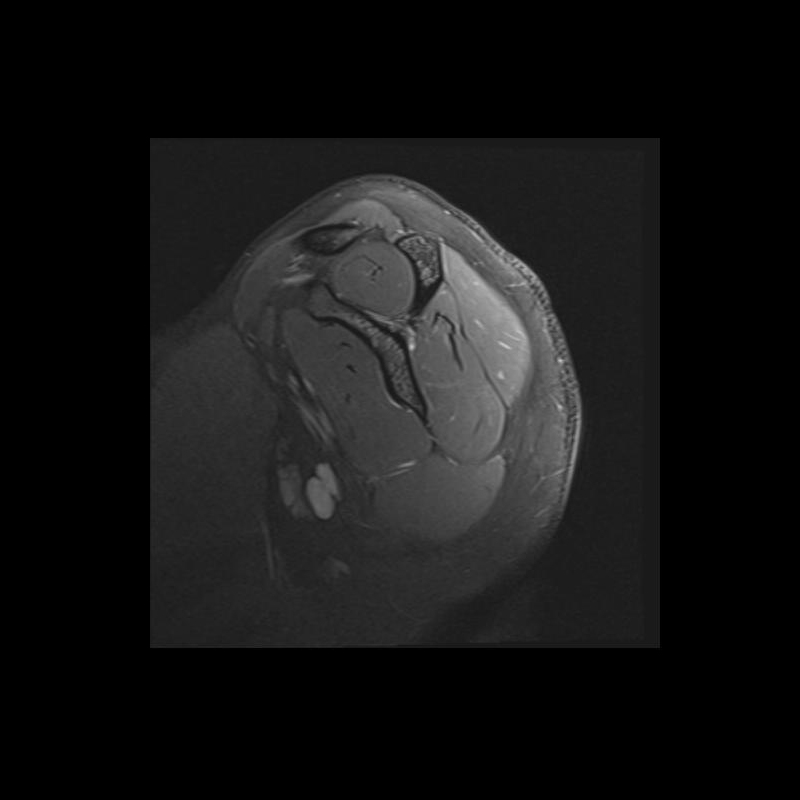

Shoulder MRI Anatomy